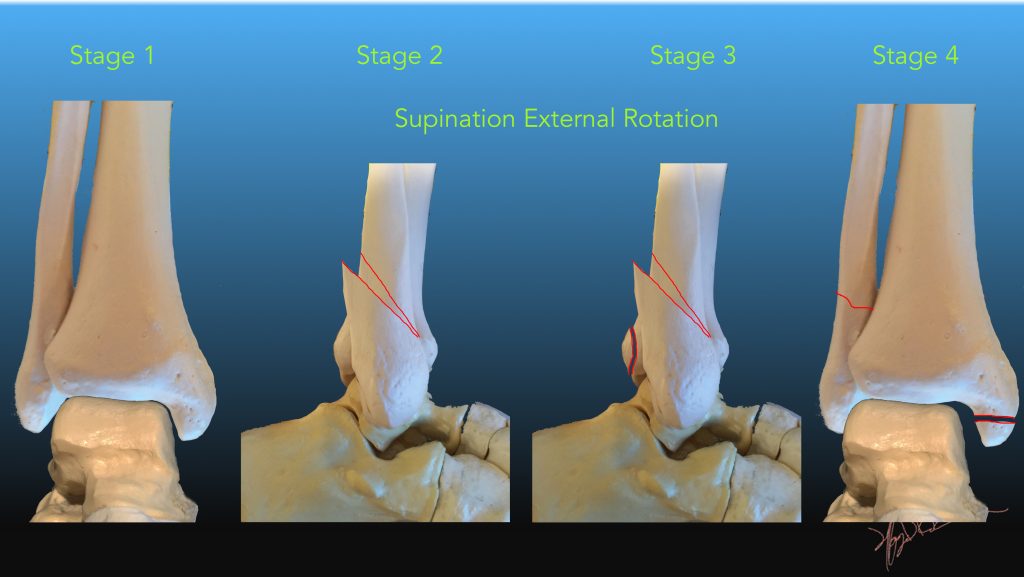

Структура и анатомия синдесмоза: научные иллюстрации